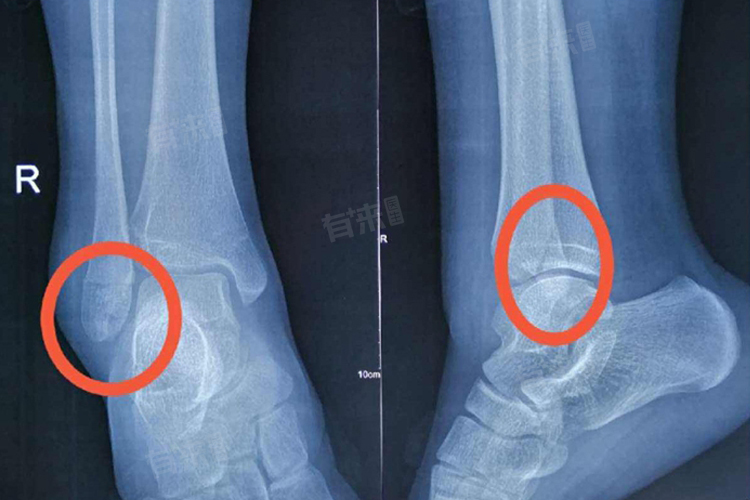

- 外踝骨折的诊断通常依赖于患者的病史、临床表现以及影像学检查,医生会询问患者的受伤经过,观察脚踝部位的症状,并进行触诊以检查是否有骨头错位。X线、CT等影像学检查也是确诊外踝骨折的重要手段,可以清晰地显示骨折的部位、形态和程度,为制定治疗方案提供重要依据。